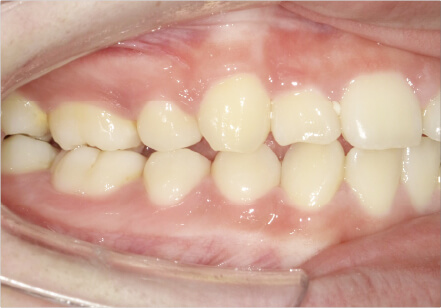

叢生の症例

41歳

/

女性

相談内容

横から見た時のガタガタが気になる

カウンセリング・診断結果

インビザライン、正中は上11に合わせていく、抜歯・拡大装置・IPR・アタッチメントOK

治療内容・方法

アライナー矯正

術後の経過・現在の様子

クリアライナー使用

治療のリスク

痛み・歯根吸収・歯肉退縮・虫歯・後戻り

費用・治療期間

880,000円、7ヶ月

トレーニングなど